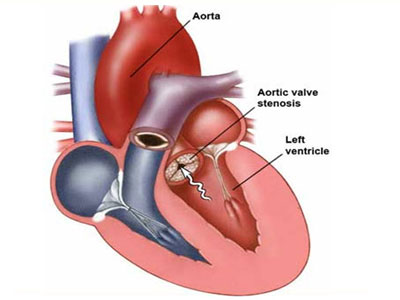

Heart valve surgery is open-heart surgery through the breastbone, into the chest. It is a major operation that can last two...